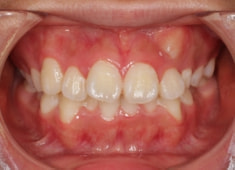

治療前

治療開始時